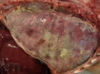

Cow - nasal granuloma (due to chronic allergic (atopic) rhinitis)

Granulomatous rhinitis - due to cryptococcus - forms thick capsule with narrow-based budding

Granulomatous rhinitis - caused by Rhinosporidium seeberi (forms polyps with huge endosporulating sporangia - endspore w/ capsule)